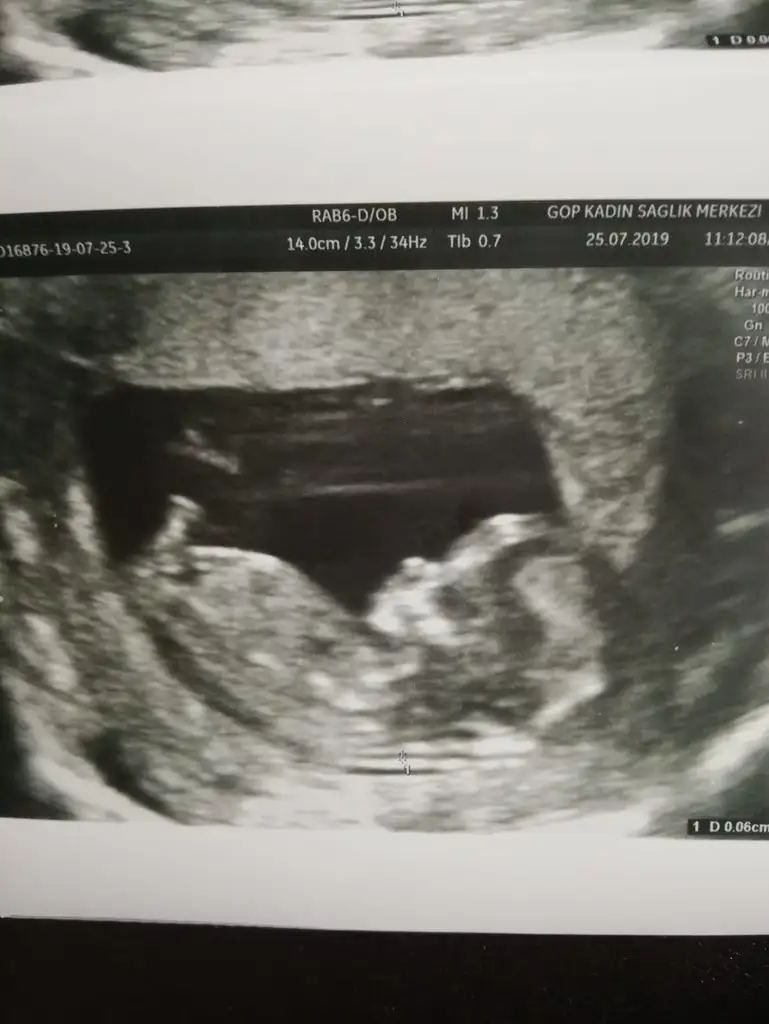

2li test için gittik ense ölçüümü gayet iyi dedi doktor 0,6mm boyu 5,25 cm tam 12+0 çıktı :)

burnu cok güzel ya fınfık burun :D

burnu cok güzel ya fınfık burun :KK70: